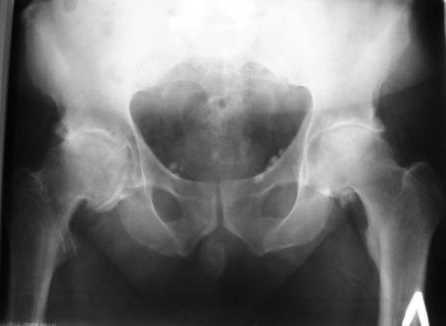

Больной Т. 56 лет, Диагноз: двухсторонний коксартроз 3-4 ст справа, 1-2 ст слева 2.10.08 выполнена операция тотальное бесцементное эндопротезирование. Использовался наружный доступ, положение на боку. Операция протекала без особенностей.

Выполнен послеоперационный ренгеноконтроль в прямой проекции. Рана зажила.

Больное выписан. Рекомендована ходьба без нагрузки 6 нед, рентгеноконтроль через 2 мес. Явка на консультацию На консультации через 7 недель- Больной ходит с дозированной нагрузкой, умеренные боли по задней поверхности правого бедра. Планируется ревизия. Удаление ножки. Установка такой же ножки Corail.

Приходилось ли кому встречаться с такой ситуацией? Вопросы: вросла ли ножка? Какие могут возникнуть сложности с удалением ножки? Нужна ли будет дополнительная трепанация диафиза? И как? Правильный выбор ножка Corail для ревизии в такой ситуации?